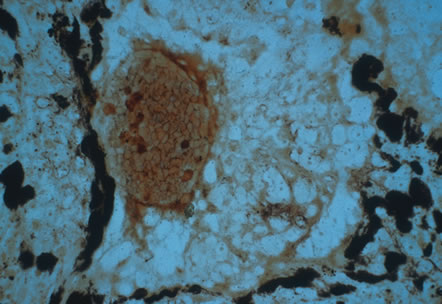

Any cell type may be infected, appearing larger than normal (cytomegalic) and demonstrating eosinophilic intranuclear “owl's eye” and smaller intracytoplasmic viral inclusion bodies, which are better seen with Giemsa or Papanicolaou's stains (Fig. 8). Histologic examination of tissue specimens, including bronchoalveolar lavage fluid and urine, may be useful for diagnosis.

Fig. 8. Typical lesion of cytomegalovirus (CMV) produces retinal necrosis with large cells possessing owl's eye inclusions.